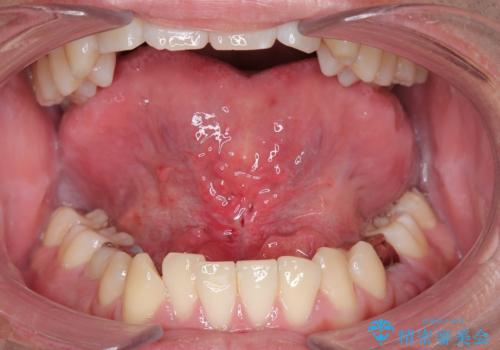

舌の可動範囲が広がり、満足していただけました。

舌小帯切除術は当日行うことができます。

- 外科手術のため、術後に出血、痛みや腫れ、違和感を伴います